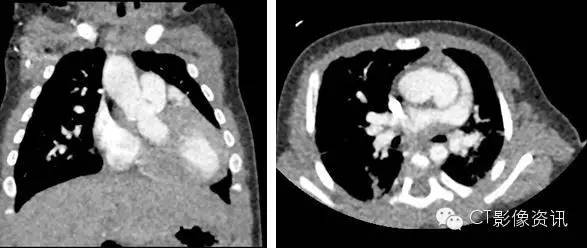

Case 1 法洛四联症 女,13 月。先天性心脏病,法洛氏四联症。

扫描协议 探测器宽度:140mm, Axial; 管电压和管电流:70kV, SmartmA; 旋转速度:0.28s/rot;迭代:ASiR-V 70%; 身高:73cm;体重:8.6kg; 对比剂:270mgI/ml, 9ml, 1.0ml/s; 扫描剂量:0.10mSv。

点评 主动脉增宽前移,骑跨于室间隔上,骑跨率约 50%。肺动脉瓣增厚,明显狭窄。主动脉、肺动脉发育差。右心房、右心室扩大。膜周部室间隔缺损,直径约 8.5mm。Revolution CT 覆盖范围大,扫描速度快,极好地避免了小儿的哭闹和移动等意外情况,并能清晰显示法洛四联症。

临床小知识 法洛四联症(Tetralogyof Fallot,TOF)是一种常见的先天性心脏畸形。其基本病理为室间隔缺损、肺动脉狭窄、主动脉骑跨和右心室肥厚。法洛四联症在儿童发绀型心脏畸形中居首位。法洛四联症患儿的预后主要取决定肺动脉狭窄程度及侧支循环情况。